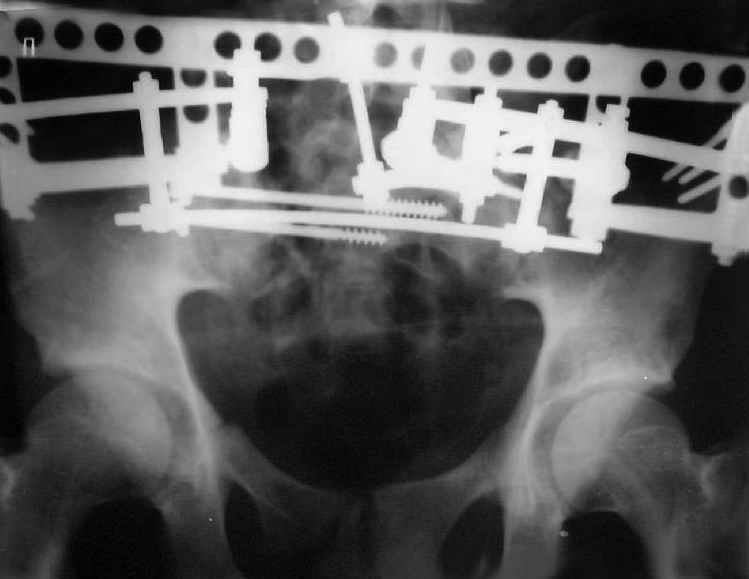

Мы, как правило, в подобных случаях проводим оперативное лечение в несколько этапов. Первым устраняем деформацию при помощи АВФ (кольцевой конструкции с фиксацией задних отделов), вторым- выполняем введение илиосакралых винтов, накостный остеосинтез передних отделов.

Для информации к размышлению о возможности исправления имеющейся деформации предлагаю похожий случай.